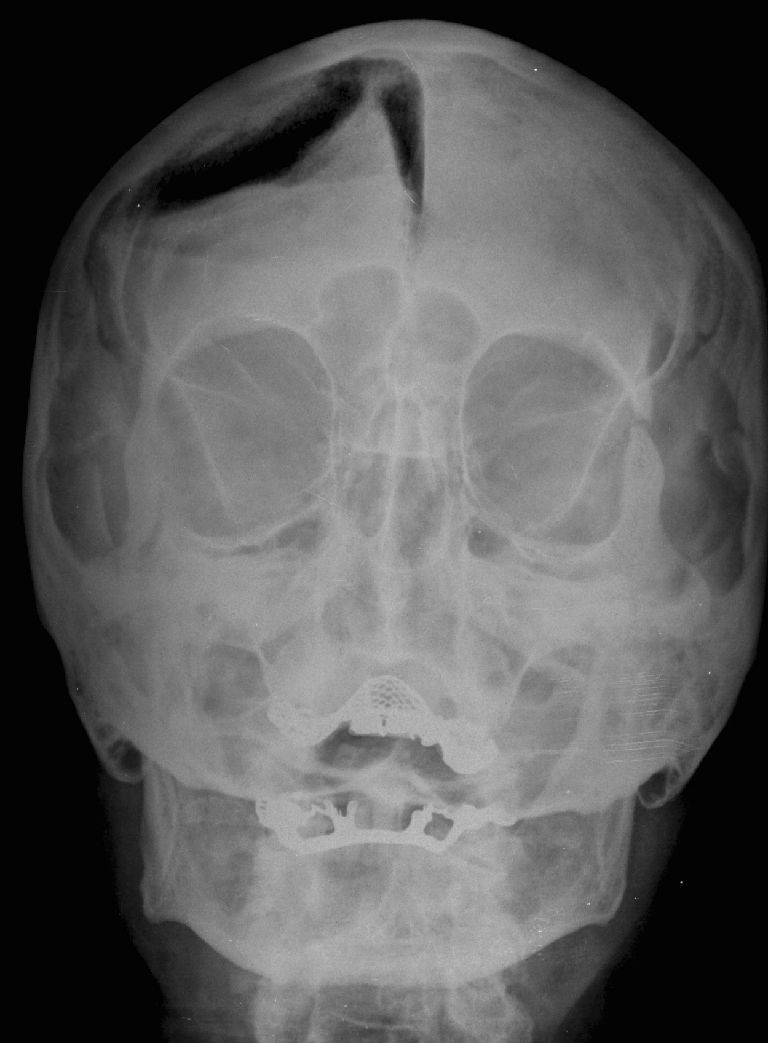

Nhờ các thực nghiệm, ông biết rằng tia X xuyên qua da thịt người nhưng không để xuyên qua những chất có mật độ cao như xương hoặc chì, và chúng có thể được chụp ảnh lại.

Phát hiện của Rontgen được xem là một phép màu y học thời đó, và tia X sớm trở thành một công cụ chẩn đoán quan trọng trong y học, cho phép các bác sĩ nhìn thấy bên trong cơ thể người mà không cần phẫu thuật.